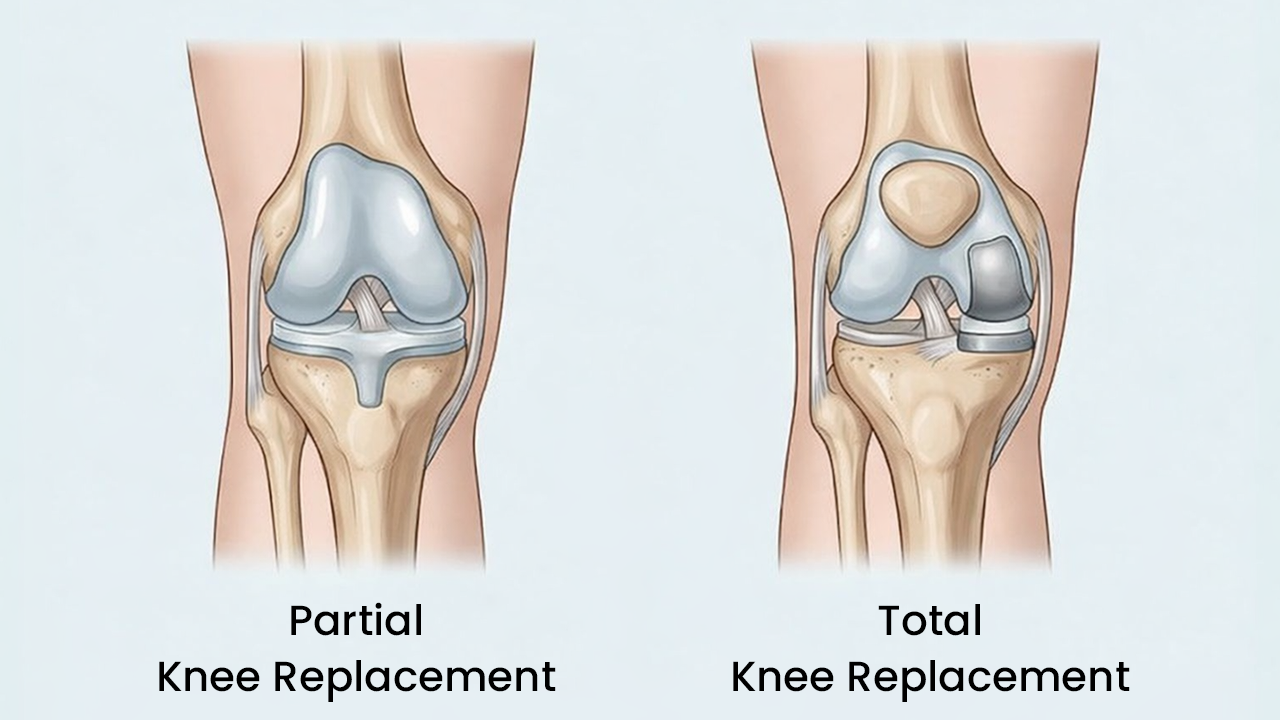

In many patients, arthritis damages only one of these compartments. The other two remain perfectly healthy.

A partial knee replacement procedure targets only the damaged compartment. The healthy bone, cartilage, and ligaments around it are left completely untouched.

Here is what that means for you:

- 75% of your natural bone is preserved

- Your ACL and PCL ligaments stay intact

- Your knee continues to feel and move like your own, just without the pain

This is the fundamental difference between partial and total knee replacement. Total replacement removes everything. Partial replacement removes only what needs to go.

Less removed. More preserved. Faster recovery.